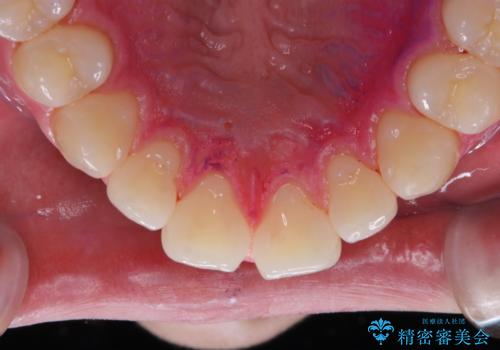

親知らずを抜いて1週間後にPMTC 歯のクリーニング

- 親知らずの抜歯後の約1週間後に抜糸(縫った部分の糸とり)で来院されました。その際、抜歯後は傷口が怖くて歯磨きが上手くできず、汚れや口臭が気になるためクリーニングも希望されました。

抜歯後は多少出血したり、違和感や痛みを感じたりすることがあります。そのため親知らずを抜いたり、外科的な処置をするといつも通りの歯磨きがしづらくなります。また、傷口の周りが心配で、歯ブラシをするのが怖くなるものです。抜歯後落ち着いたら、歯科医院にて専門の機械を使用しクリーニングをすることがおすすめです。抜歯前や後にPMTCを行うことで、お口の中の健康維持につながり、その後の感染・腫れ・口臭予防などになります。

親知らず抜歯後正常に治癒が進んでいれば1週間後から可能です。